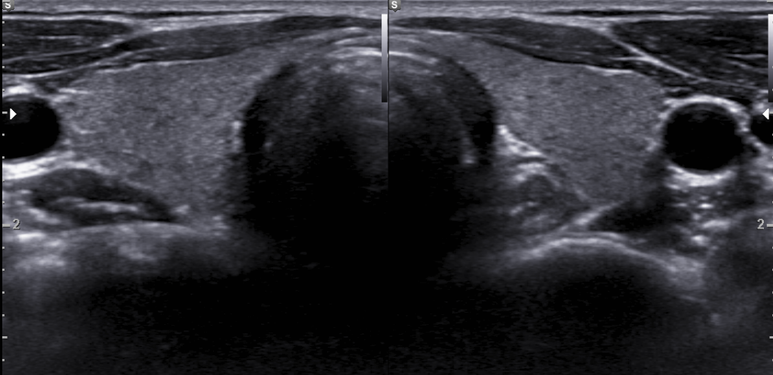

2016.11월 검진차 내원

저음영의 미세결절 변화는 매우 두드러지고 갑상선 비대해짐

갑상선염 소견 진행

결절의 크기가 증가함